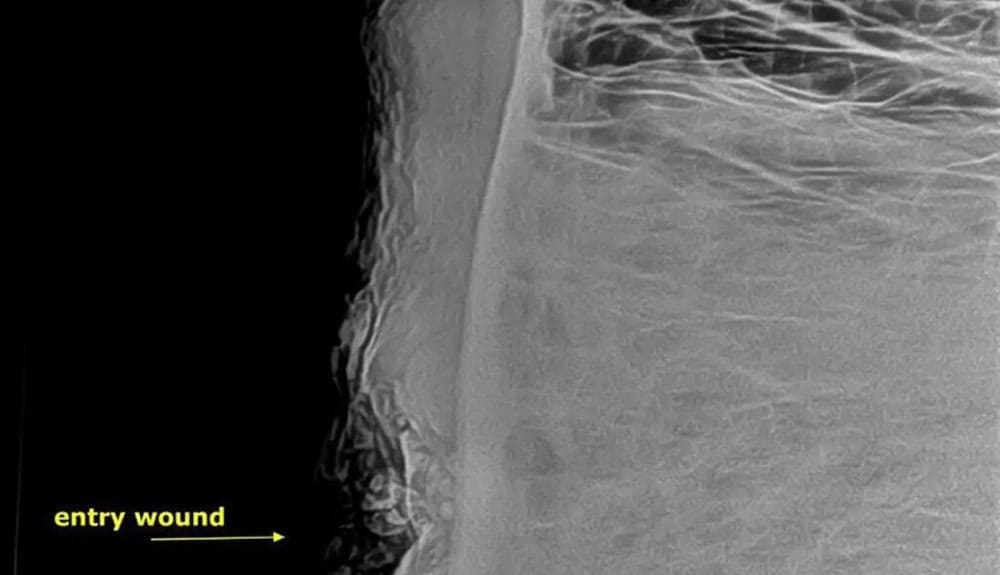

X-rays revealed a deformed bullet lodged in his skull, causing significant damage but narrowly missing vital structures.

Dr. Lisa Marabini, AWARE’s director, explained that while the bullet caused substantial damage, Pretty Boy’s life was spared thanks to its trajectory.